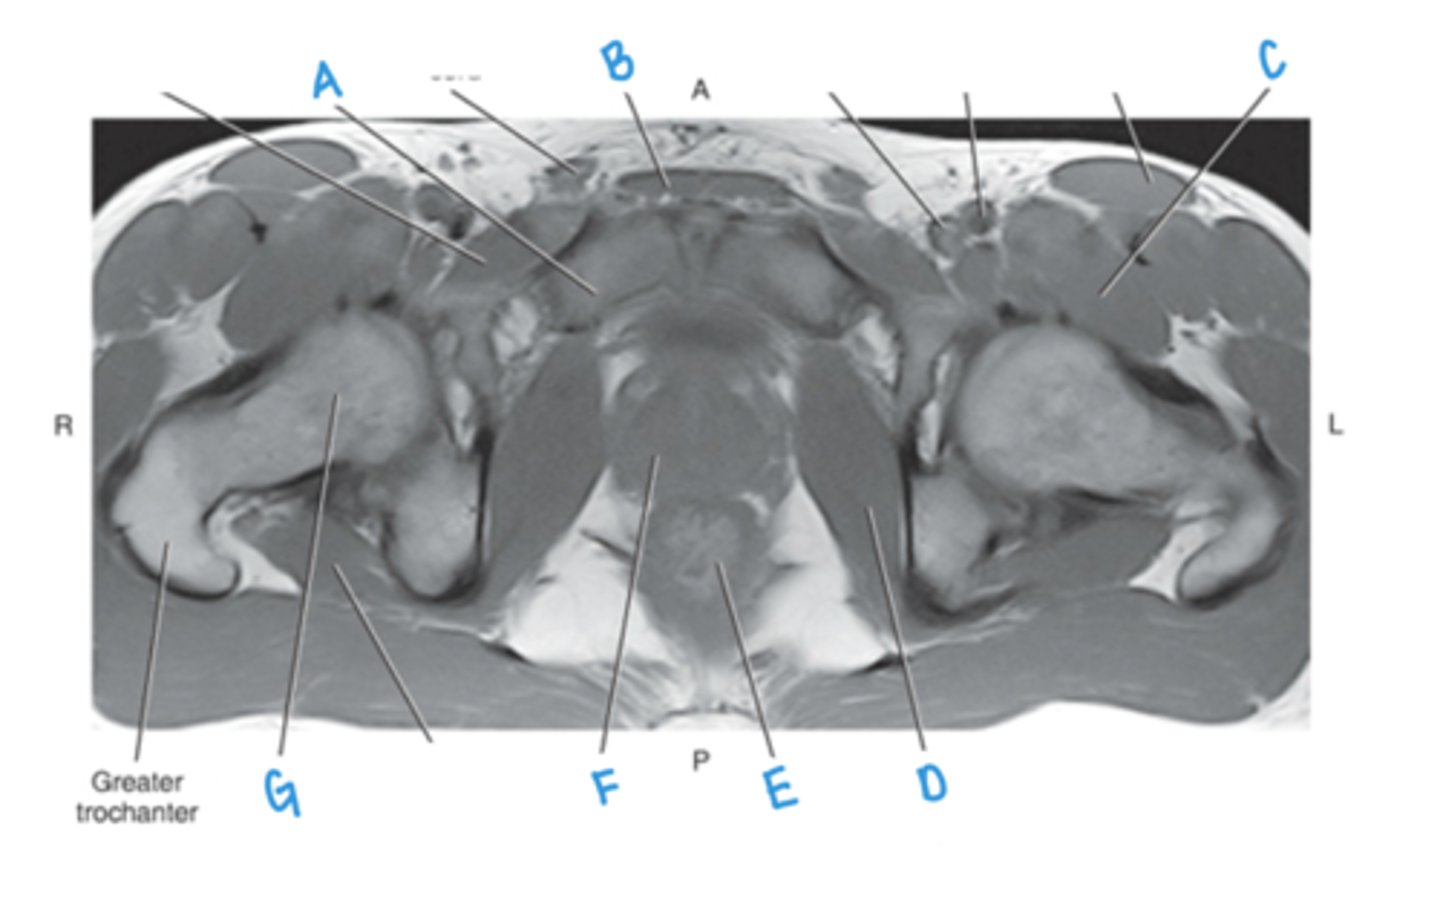

ureter

A & F

small intestine

B

bladder

C

prostate

D

sigmoid colon

E

iliacus muscle

G

psoas major muscle

H